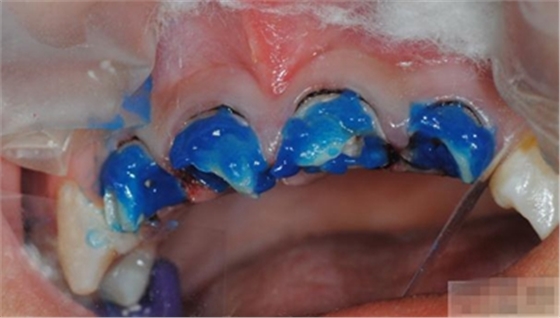

【酸蝕粘結(jié)】

使用磷酸酸蝕可用完全去除玷污層,粘結(jié)劑可用充分滲透到牙本質(zhì)小管中。用自酸蝕系統(tǒng)則達(dá)不到這一點(diǎn),由于其不能充分去除玷污層,粘結(jié)劑向牙本質(zhì)小管內(nèi)的滲透率低。所有的研究均顯示,使用全酸蝕系統(tǒng)所形成的粘結(jié)混合層要比使用自酸蝕系統(tǒng)厚。

酸蝕處理的時(shí)間

a,活髓牙本質(zhì)酸蝕30秒;

b,硬化牙本質(zhì)酸蝕60秒;

c,根管內(nèi)如果需粘結(jié)根冠樁,需酸蝕2分鐘。